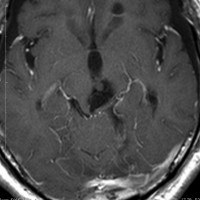

静脈性血管腫(静脈奇形)の合併を見つける方法

左は脳出血のCTです。海綿状血管腫からの出血を疑ったので造影のMRI(右の写真)をしました。血腫の周りに細い線がたくさん見えます。これが静脈奇形(静脈性血管腫)です。脳血管撮影DSAをしなくてもこの合併はわかるのです。この静脈奇形を手術で傷つけるとかなり広い範囲で脳梗塞がおきる可能性があります。